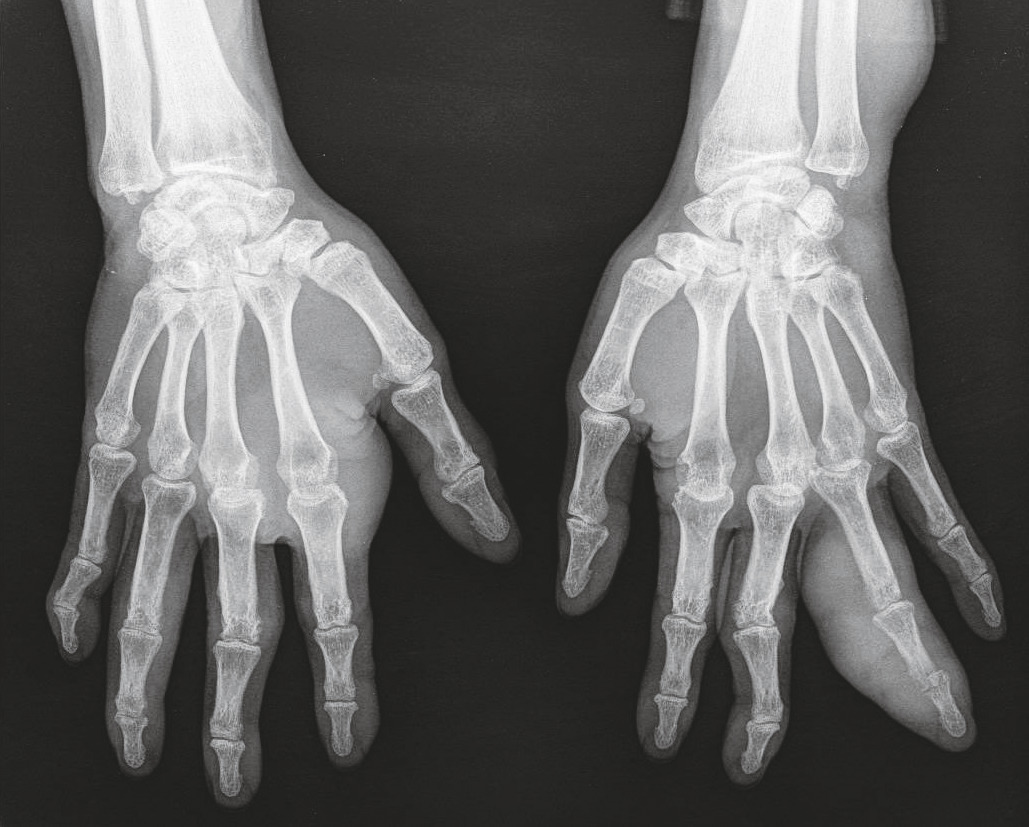

Un homme de 64 ans, avec un indice de masse corporelle à 20, originaire du Laos, ex-pratiquant de boxe thaï, présente des gonflements articulaires des mains évoluant depuis plus de huit mois, sans douleur (fig. 1 ). Cliniquement et à la radio (fig. 2 ), on observe un tophus de 5 centimètres sur 5 au niveau de la 2e articulation métacarpo-phalangienne à droite et une dactylite du 4e rayon à gauche, avec des tophus en voie d’abcédation (fig. 3 ). L’acide urique est dosé à 608 µmol/L, sans syndrome inflammatoire associé.